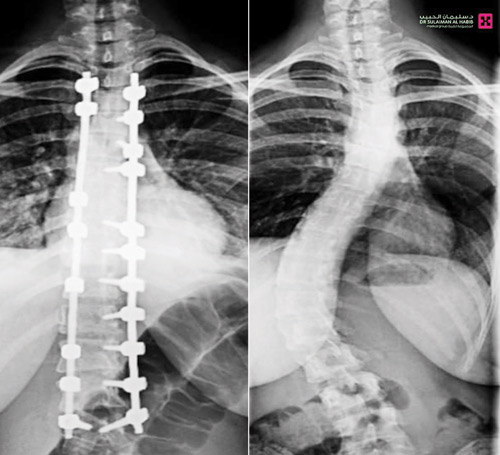

تمكّن فريق طبي في مستشفى الدكتور سليمان الحبيب بالصحافة، من إجراء عملية نوعية ناجحة لتقويم تشوّه متطور بالعمود الفقري لشابة عشرينية، كانت تعاني من ميلان (جنف) بدرجة «55» وتحدّب صدري بمقدار «70» درجة، ما سبّب لها صعوبات في الجلوس والمشي بشكل مستقيم، وأثّر سلبًا على حياتها الاجتماعية والنفسية، ذكر ذلك د. تركي العنزي استشاري المخ والأعصاب وجراحات العمود الفقري المعقّدة، رئيس الفريق الطبي المعالج.

وأوضح د. العنزي أن الفحوصات التي أجريت للمريضة أظهرت وجود ميلان وتحدب متزايد يتطلب تدخلاً جراحيًا عاجلًا. وبعد دراسة الحالة، تقرّر إجراء عملية لتصحيح التشوّه وتحسين المظهر الخارجي للظهر. وأضاف أن العملية استغرقت «5» ساعات، وأُجريت تحت المراقبة العصبية الدقيقة، وشملت تصحيح العمود الفقري على امتداد «12» فقرة عبر تثبيتها ودمجها باستخدام أحدث أنظمة التثبيت الجراحي، مع إغلاق تجميلي للجرح بتقنيات متقدمة تضمن تقليل الآثار مستقبلاً، إضافة إلى إعادة توازن الكتفين وتناسق الخصر.

وبيّن د. العنزي أن المريضة بدأت بالمشي صباح اليوم التالي للعملية، وغادرت المستشفى بعد خمسة أيام من العملية وقد استعادت قدرتها على الجلوس والمشي والنوم بشكل مريح. كما أن طولها زاد بما لا يقل عن «10» سم نتيجة تصحيح الانحناء.